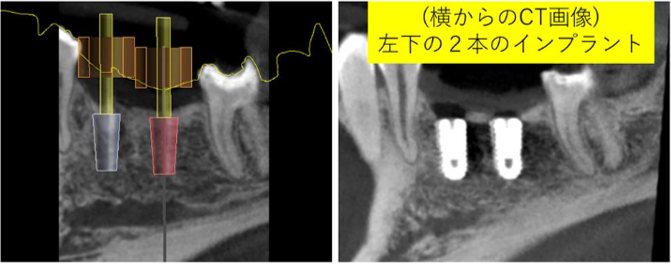

シミュレーションソフトを用いた、安全なインプラントの症例

骨が足らない時のインプラント:ガイドとソケットリフトを用いたインプラント症例

残った歯を守るためにインプラントを行った症例